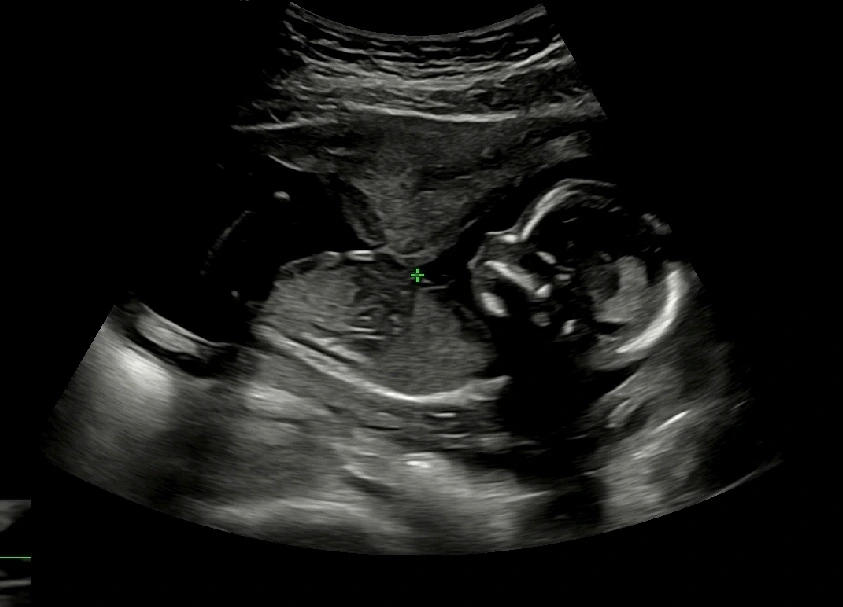

임신 17주차 초음파 사진

한 달이 아닌 한 주 후에 다시 병원에 갔다. 두 번째 초음파 사진처럼 양쪽 다리에 아무 것도 보이지 않는 것처럼 우리 집에는 딸이 찾아왔다 :) 16주차와 또 다르게 더욱 사람의 모습을 하고 있는 반짝이! #임신17주초음파